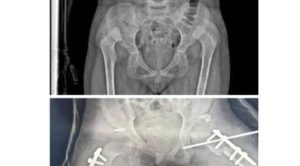

في إطار الرسالة السامية الذي يقدمها كوادر مستشفى الشحر العام ورغم شحة الإمكانيات أجريت بنجاح عملية ارجاع خلع خلقي لمفصل الورك ( DDH ) لطفلة تبلغ ٧ سنوات ونص.

و تكون كادر العملية من الدكتور سالمين عوض باحسن اخصائي جراحة العظام والتشوهات ودكتور عبدالله عبدالله بن فاتح اخصائي التخدير وفني العمليات سعيد محيمود ومعتز بن سلوم وفنية التخدير ليلى القرزي وافراح العجيلي.

و أشاد الأستاذ سالم محمد الغرابي مدير مستشفى الشحر العام بنجاح العملية وبالجهود العظيمة التي يبذلها الكادر الطبي بالمستشفى ، كما أكد أن الكوادر الطبية تعمل بتفانٍ وإخلاص رغم التحديات الكبيرة وشحة الإمكانيات التي تواجه المستشفى موضحا أن المستشفى يواصل تقديم خدماته الطبية المتنوعة، حيث يتم إجراء العديد من العمليات الجراحية مثل العمليات القيصرية ، عمليات الأذن والأنف والحنجرة ، العمليات الجراحية بمختلف أنواعها ، عمليات العظام.